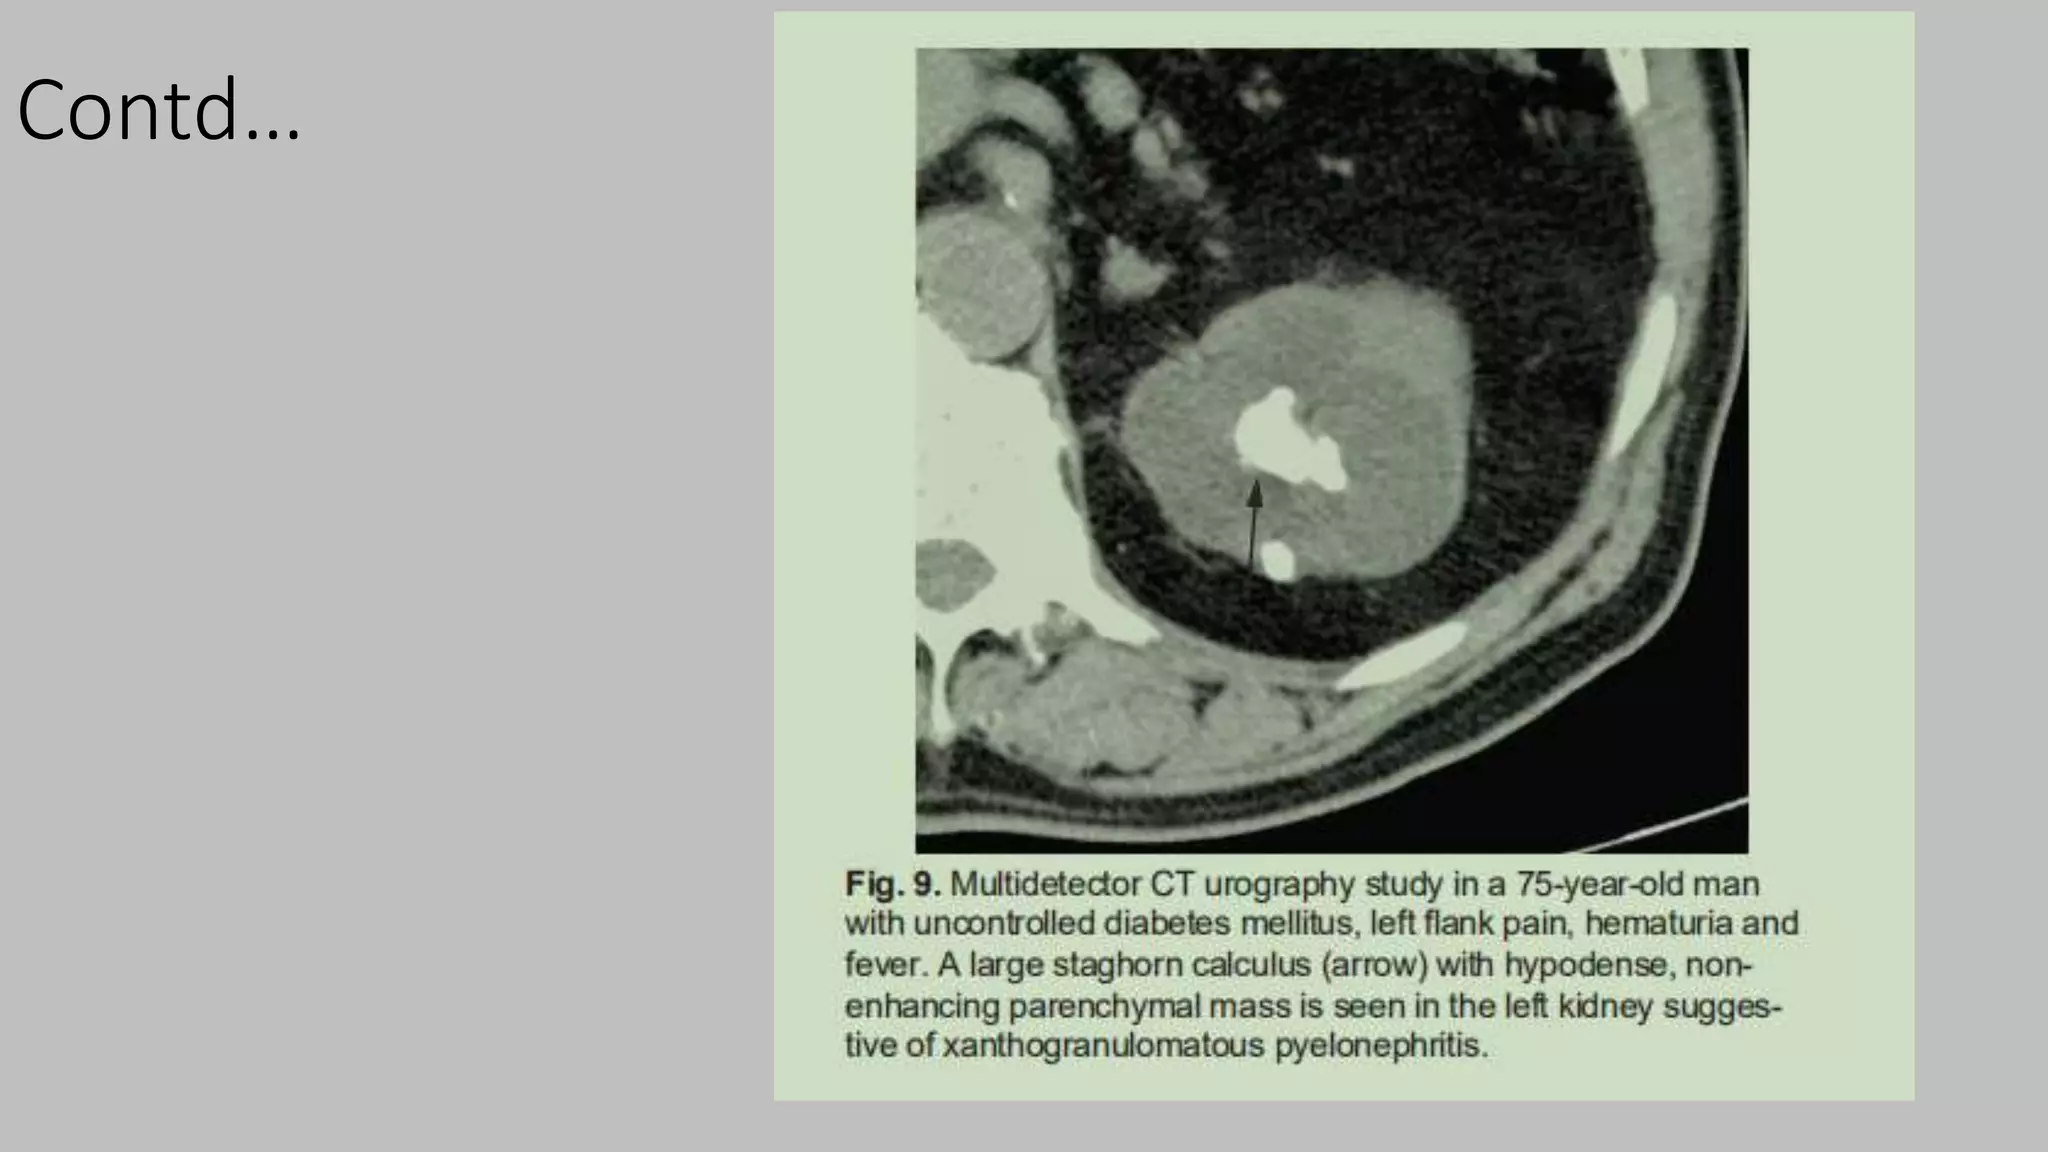

Contd..

Contd…

• #55 Xanthogranulomatous pyelonephritis (XGP), first described by Schlagenhaufer in 1916, is a rare, serious, chronic inflammatory disorder of the kidney characterized by a destructive mass that invades the renal parenchyma